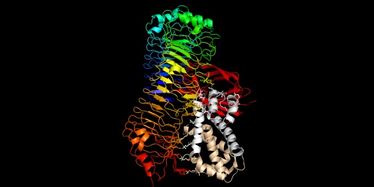

New article published in "The Journal of Neuroscience" (Volume 38, Issue 38)

New article published in "The Journal of Neuroscience" (Volume 38, Issue 38)